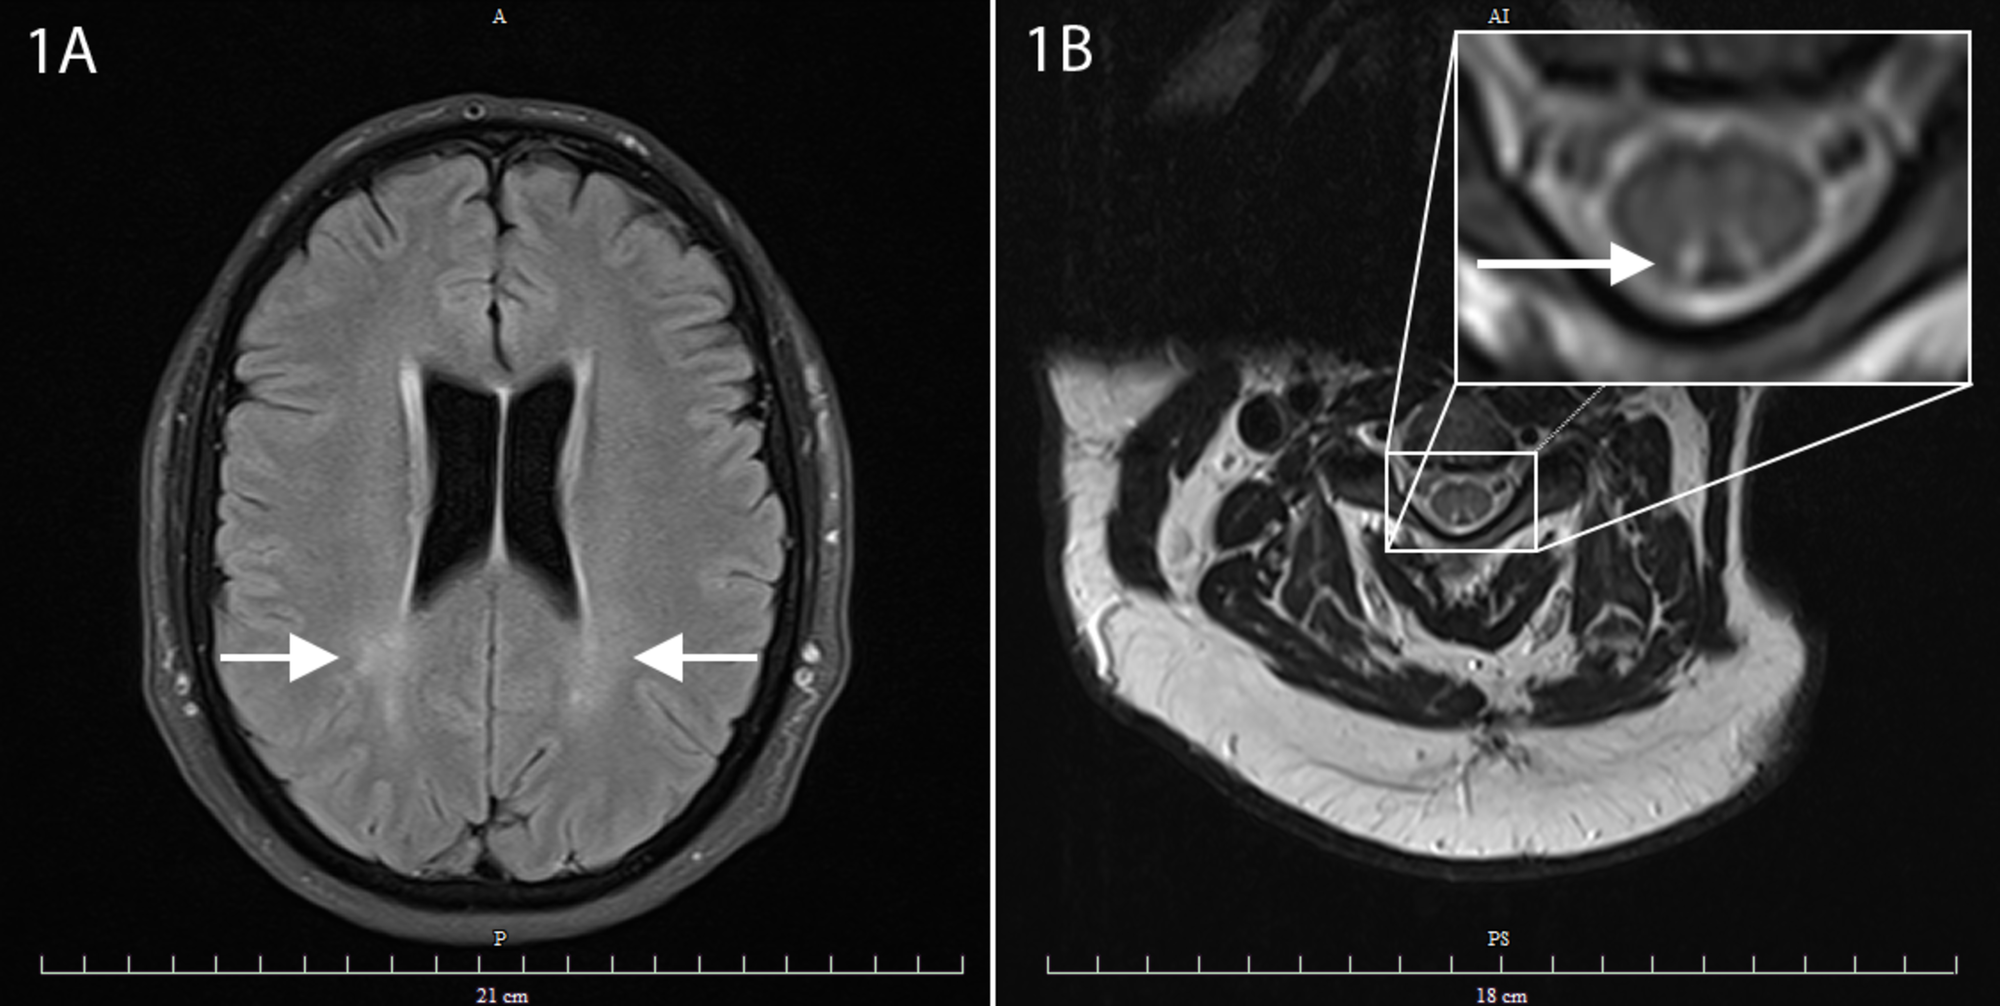

From www.cureus.com

Subacute Combined Degeneration of the Spinal Cord Secondary to Nitrous Nitrous Oxide Multiple Sclerosis Its involvement in multiple sclerosis (ms) had. Its involvement in multiple sclerosis (ms) had. Nitric oxide (no) is a free radical found at higher than normal concentrations within inflammatory multiple sclerosis (ms) lesions. Nitric oxide (no) is a free radical found at higher than normal concentrations within inflammatory multiple sclerosis (ms) lesions. These high concentrations are due to the. Nitric. Nitrous Oxide Multiple Sclerosis.

Cureus Nitrous Oxide Induced Posterior Cord Myelopathy Beware of the Nitrous Oxide Multiple Sclerosis Its involvement in multiple sclerosis (ms) had. Its involvement in multiple sclerosis (ms) had. Nitric oxide (no) is a free radical found at higher than normal concentrations within inflammatory multiple sclerosis (ms) lesions. This article reviews the role of nitric oxide in the biology of central nervous system glial cells (astrocytes and microglia) as it pertains to the. Nitric oxide. Nitrous Oxide Multiple Sclerosis.

Cureus Nitrous Oxideinduced B12 Deficiency Presenting With Nitrous Oxide Multiple Sclerosis Nitric oxide (no) is a free radical signaling molecule with remarkably complex biochemistry. Its involvement in multiple sclerosis (ms) had. Inducible nitric oxide synthase (inos) is an enzyme that produces nitric oxide (no) and is thought to contribute to the pathogenesis of. Its involvement in multiple sclerosis (ms) had. Nitric oxide (no) is a free radical signaling molecule with remarkably. Nitrous Oxide Multiple Sclerosis.